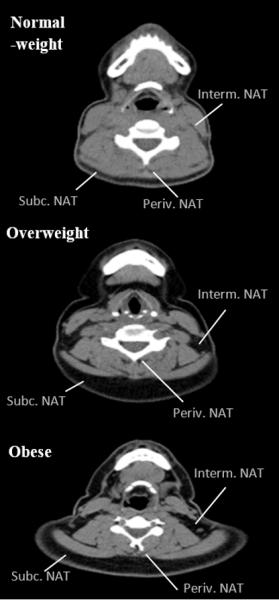

image: This figure shows the accumulation of fat in different neck deposits (subcutaneous, intermuscular, and paravertebral) in a person of healthy weight, an overweight person, and an obese person. It can be observed that accumulation of fat in the different deposits of the neck increases as overall adiposity increases in the participants.

"Curiously, several studies have demonstrated that the accumulation of fat in the neck (both superficial deposits such as the double chin or jowls and the deeper deposits, located between the muscles and around the cervical vertebrae) increases in direct proportion to the weight or adiposity of the individual and that it follows specific accumulation patterns, according to gender," explains María José Arias Téllez, a researcher at the UGR and one of the main authors of this work. In fact, a greater accumulation of fat in certain neck tissue compartments, particularly the deeper ones, is linked to a greater likelihood of cardiometabolic risk. Arias Téllez continues: "However, the evidence accumulated to date has been based on experiments performed on patients with benign/malignant tumours or other chronic conditions, and it remains to be seen whether it can be generalised to relatively healthy adults."

The study shows that the accumulation of fat in the neck--measured with computed tomography scanning--as well as its distribution in different compartments, is associated with greater overall and central adiposity, greater cardiometabolic risk, and a greater inflammatory status among healthy young adults, regardless of the amount of total and visceral fat. In addition, among the most relevant findings, it was observed that this accumulation of fat in the neck was as powerful a factor (in terms of direction and magnitude) as the accumulation of visceral fat in the prediction of cardiometabolic risk and inflammatory status, especially in men.